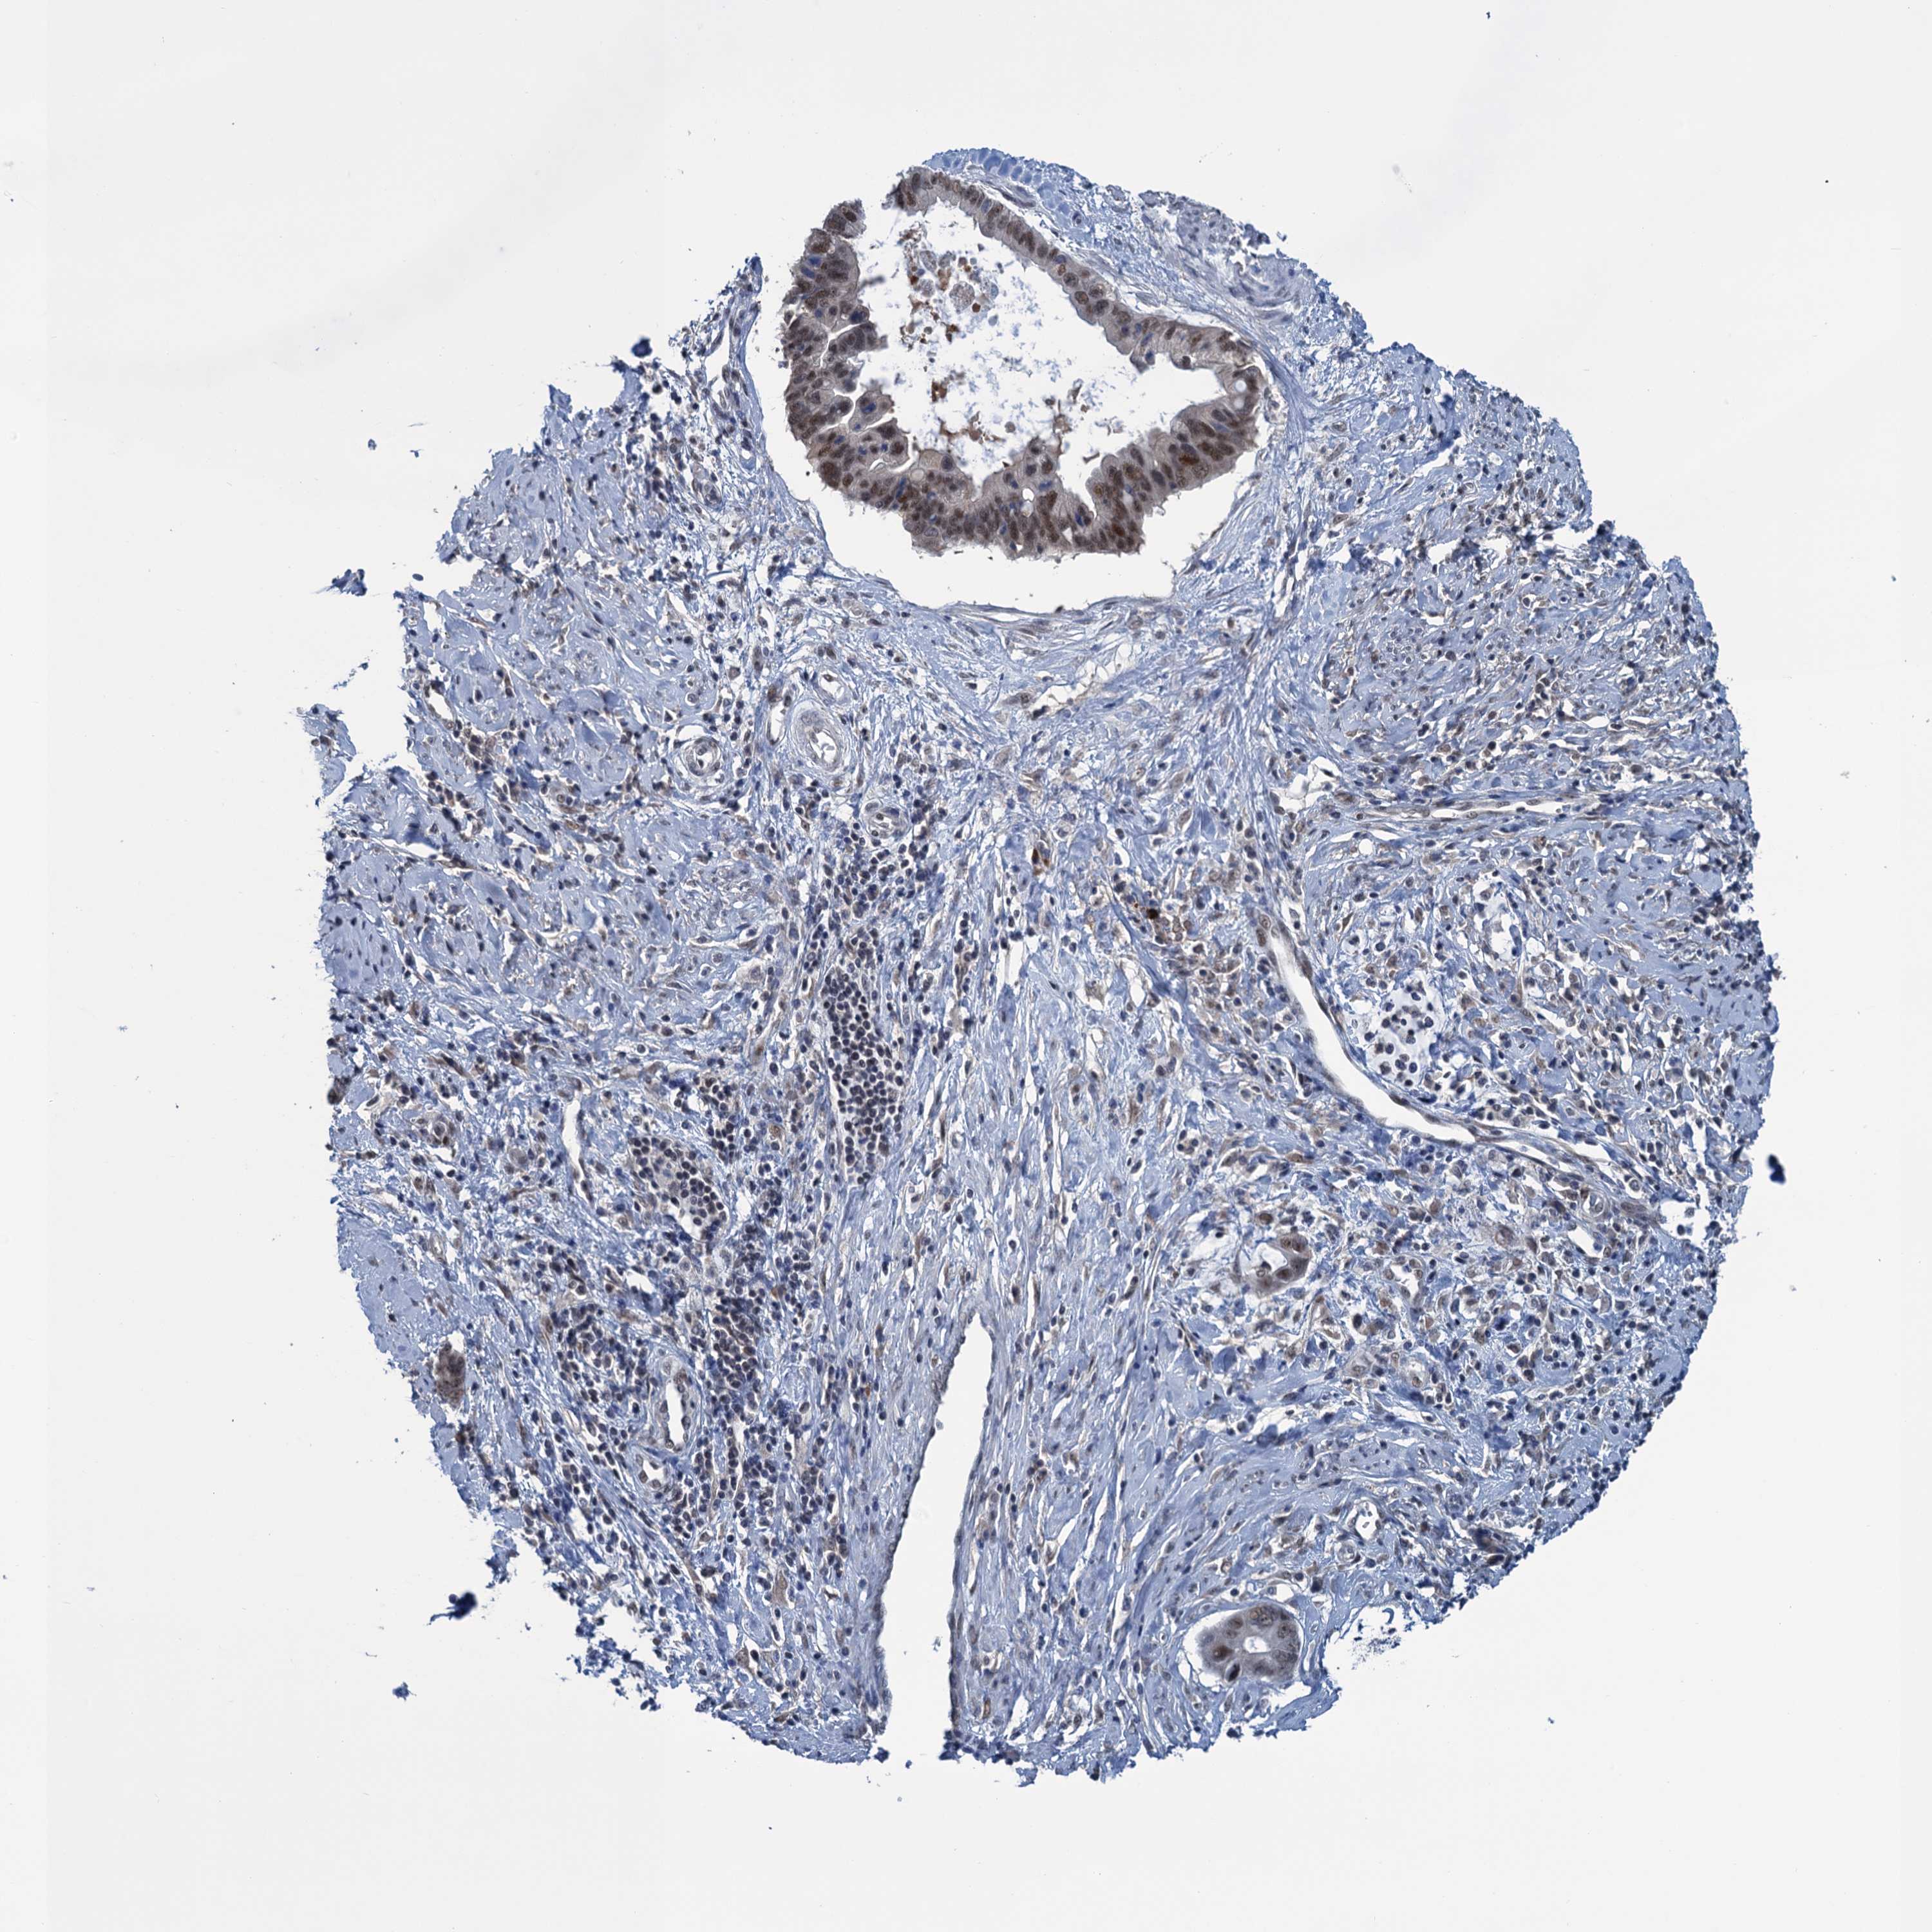

CERVICAL CANCER - Protein expressioni

A mouse-over function shows sample information and annotation data. Click on an image to view it in a full screen mode. Samples can be filtered based on level of antibody staining by selecting one or several of the following categories: high, medium, low and not detected. The assay and annotation is described here.

Note that samples used for immunohistochemistry by the Human Protein Atlas do not correspond to samples in the TCGA dataset.

Antibody stainingi

Antibody staining in the annotated cell types in the current human tissue is reported as not detected, low, medium, or high, based on conventional immunohistochemistry profiling in selected tissues. This score is based on the combination of the staining intensity and fraction of stained cells.

Each image is clickable and will lead to virtual microscopy that enables deeper exploration of all samples and also displays staining intensity scores, fraction scores and subcellular localization as well as patient and tissue information for each sample.

Antibody HPA041906

Antibody HPA043552

Staining

High

Medium

Low

Not detected

Intensity

Strong

Moderate

Weak

Negative

Quantity

>75%

75%-25%

<25%

None

Location

Nuclear

Cytoplasmic/membranous

Cytoplasmic/membranous,nuclear

Squamous cell carcinoma, NOS

Adenocarcinoma, NOS